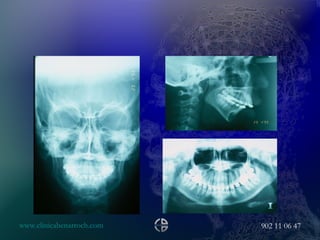

LR, F, 21.July, 2000 PROBLEM LIST Ocular surface disease Nasal deformity Lower third vertical augmentation Upper and lower lip deformity Maxillary transverse collapse AP chin deficiency Vertical chin augmentation SURGICAL PLAN 2 PHASES Maxillary assisted expansion Maxillary posterior impaction Mandible BSS Lip pasties Vertical reduction of the chin AP chin advancement

• #79 Maxillary assisted expansion with the same protocol of the last case, the orthodontics star to move the central incisors after 4 months

• #80 10 month after de expansion

• #82 13 months after surgery